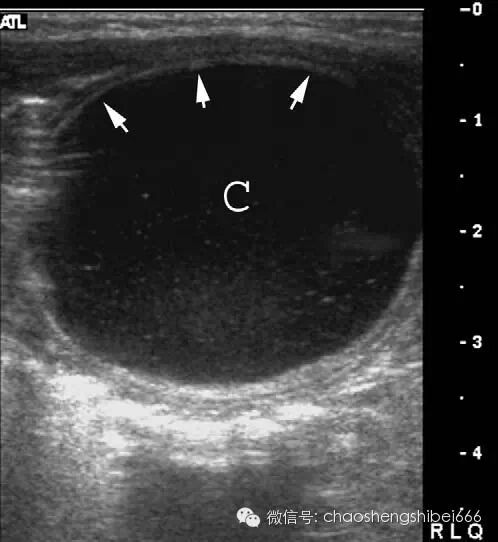

肠重复畸形(囊肿)

典型的肠重复畸形的囊肿超声显示为有特征性的双层囊壁,内层为高回声代表粘膜,外层为低回声的肌层(图9)。如果合并感染则分层的结构会消失,降低了诊断的特异性。无论如何,超声发现囊性肿物与肠管毗邻都应考虑到肠重复畸形的存在。

9 肠梗阻女婴,梗阻继发于肠重复畸形扭转。肠重复囊肿(C)直径87.5px,部分囊壁为特征性的双层结构,内层为强回声粘膜(箭头),外层为低回声肌层。

肠重复畸形是一种可以发生于消化道任意地方的先天异常,最常见的发生部位是从食管,其次为回肠末端。典型的是小儿在新生儿时的囊性含液性性病变。如果囊肿内被覆的是胃粘膜,它可以分泌酶类而导致感染和疼痛。